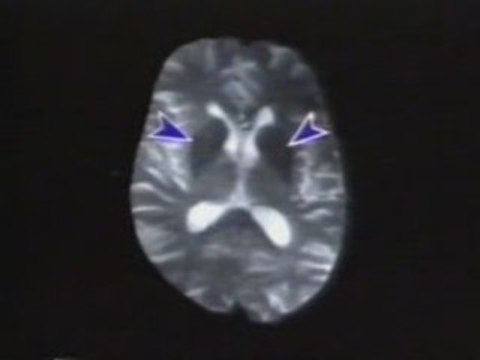

¿Cuánto tiempo dura el período de pérdida de células neuronales cuando se está enfermo de Parkinson? ¿Qué factores aceleran la pérdida de neuronas en la enfermedad de Parkinson? Consulte a su Médico. De la mano de un médico, te daremos a conocer información muy interesante. De las dudas que normalmente tenemos, te daremos a conocer respuestas directamente de expertos en el tema.